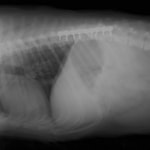

症例:交通事故による椎体脱臼

柴犬:9歳、避妊雌

交通事故直後、胸腰部に激しい疼痛、両後肢に完全麻痺を認め、シェフシェリントン徴候を呈していました。レントゲン検査において、第11-12胸椎間の脱臼が認められました。

脊髄の減圧、脊柱管の再構築・安定化を目的に、片側椎弓切除術およびMatrixMANDIBLE Plateによる椎体固定を実施しました。

隣接椎体を架橋するようにプレートを設置しました。

術後レントゲン写真